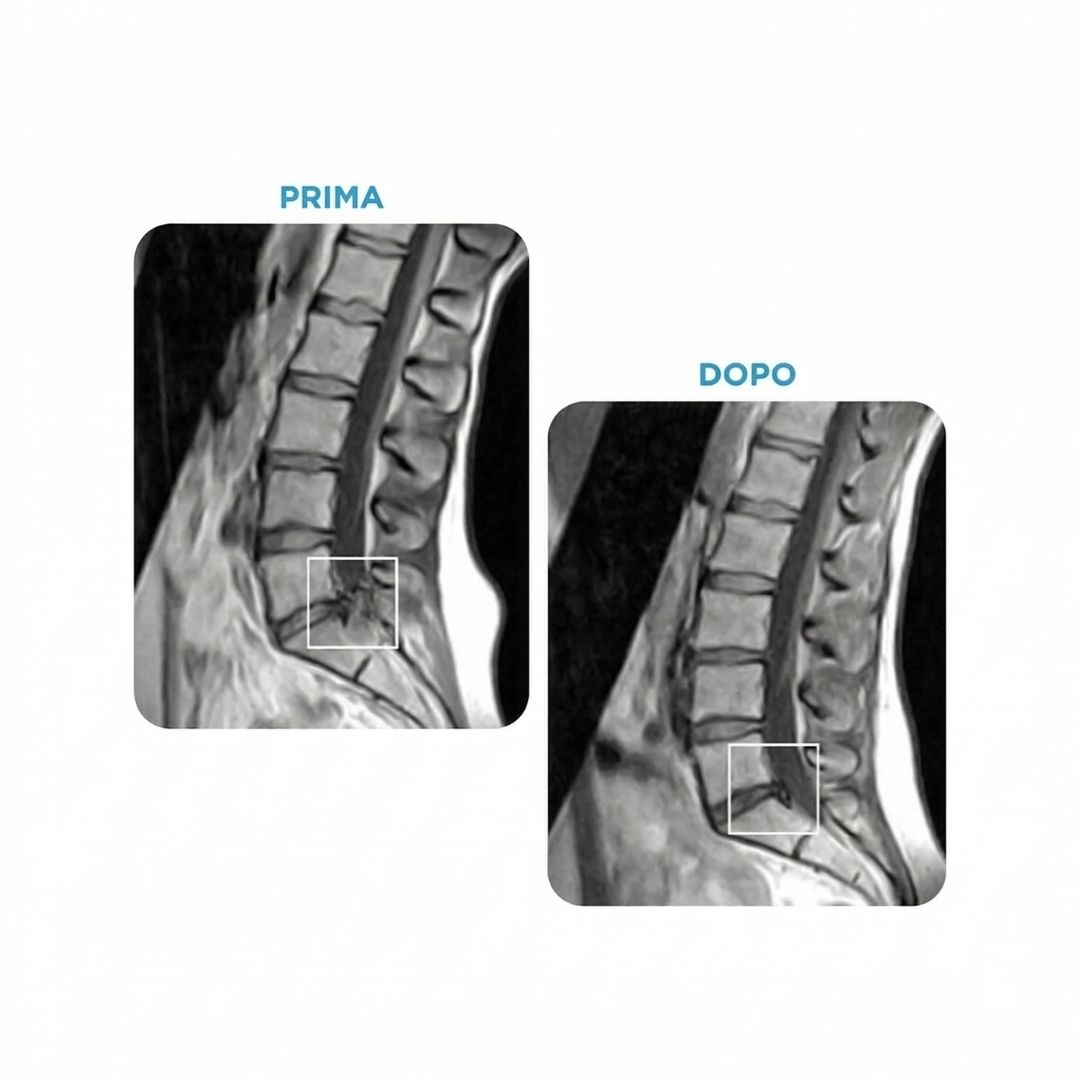

Decompressione Spinale Roma - Prima e dopo il trattamento: riduzione della pressione discale e rientro dell'ernia presso lo Spine Center Phisiotop Roma Morena

Effetto della Decompressione Spinale: prima e dopo il trattamento sul disco intervertebrale